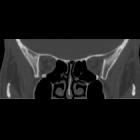

Inferior blowout fracture

Inferior blowout fractures are the most common. Orbital fat prolapses into the maxillary sinus and may be joined by prolapse of the inferior rectus muscle. In children, the fracture may spring back into place (see trapdoor fracture). Most fractures occur in the floor posterior and medial to the infraorbital groove .

In ~50% of cases, inferior blowout fractures are associated with fractures of the medial wall .

Medial blowout fracture

Medial blowout fractures are the second most common type, occurring through the lamina papyracea. Orbital fat and the medial rectus muscle may prolapse into the ethmoid air cells.

CT

CT is the modality of choice for assessment of the facial skeleton. A full assessment does not require the administration of contrast. Ideally, the acquisition should be performed using the thinnest detector settings, enabling thin-slice reconstructions along three orthogonal planes with a bone algorithm. Additional soft tissue algorithm reconstructions using larger slice thickness and 3D volumetric reconstruction are useful for assessing associated soft tissue injury and gauging facial asymmetry, respectively.